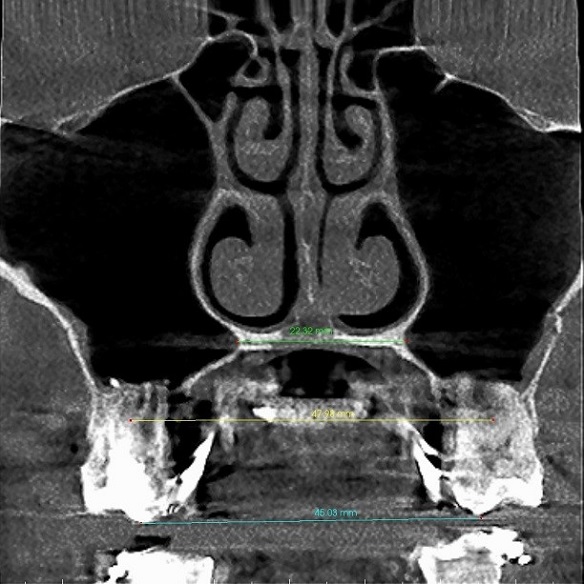

Rzut osiowy podniebienia po ekspansji u osoby dorosłej – widoczne równoległe rozejście się szwu podniebiennego na całej długości: